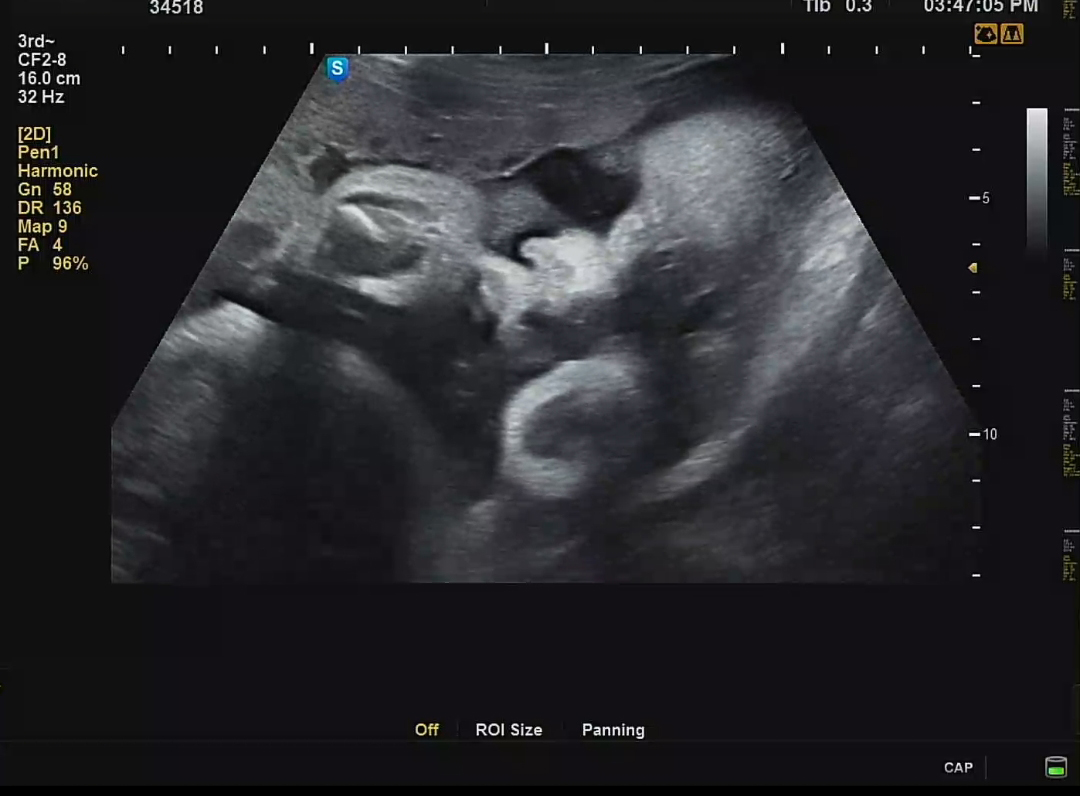

차츰 주수가 늘어날수록 초음파 영상에 꽉 차는 까꿍이 모습. 이제는 양수가 줄어들면서 태아가 차지하는 공간이 많아지는 시기기 때문에 더 그러는 것 같다. 제한된 공간에서 손을 웅크리고 있는 까꿍이. 역시나 얼굴보기 힘들었지만 잠깐이나마 가까스로 언 듯 보이는 까꿍이 얼굴이 너무 반갑다.

확실히 예전에는 얇상했다면, 이번 초음파에서는 볼살과 얼굴이 통통해졌음을 느낄 수 있었다..ㅋㅋ 귀여워😍🧡💕